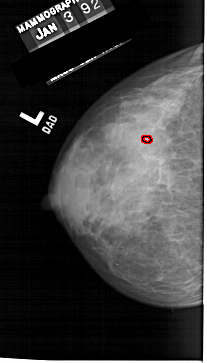

A_1257_1.LEFT_CC

LEFT_CC LINES 5806 PIXELS_PER_LINE 3301 BITS_PER_PIXEL 12 RESOLUTION 43.5 OVERLAY

FILE: A_1257_1.LEFT_CC.OVERLAY

TOTAL_ABNORMALITIES 1

ABNORMALITY 1

LESION_TYPE CALCIFICATION TYPE PLEOMORPHIC DISTRIBUTION CLUSTERED

ASSESSMENT 4

SUBTLETY 1

PATHOLOGY MALIGNANT

TOTAL_OUTLINES 1

BOUNDARY